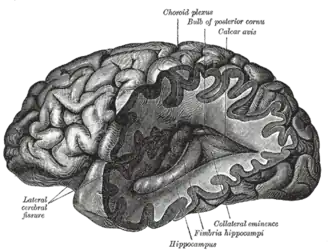

Neuroimaging is the use of quantitative (computational) techniques to study the structure and function of the central nervous system, developed as an objective way of scientifically studying the healthy human brain in a non-invasive manner. Increasingly it is also being used for quantitative research studies of brain disease and psychiatric illness. Neuroimaging is highly multidisciplinary involving neuroscience, computer science, psychology and statistics, and is not a medical specialty. Neuroimaging is sometimes confused with neuroradiology.

Neuroradiology is a medical specialty that uses non-statistical brain imaging in a clinical setting, practiced by radiologists who are medical practitioners. Neuroradiology primarily focuses on recognizing brain lesions, such as vascular diseases, strokes, tumors, and inflammatory diseases. In contrast to neuroimaging, neuroradiology is qualitative (based on subjective impressions and extensive clinical training) but sometimes uses basic quantitative methods. Functional brain imaging techniques, such as functional magnetic resonance imaging (fMRI), are common in neuroimaging but rarely used in neuroradiology. Neuroimaging falls into two broad categories:

- Structural imaging, which is used to quantify brain structure using e.g., voxel-based morphometry.

- Functional imaging, which is used to study brain function, often using fMRI and other techniques such as PET and MEG (see below).